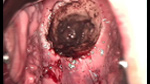

• CIN 2-3 修復(fù)后CIN 2-3 修復(fù)后

• CIN 2-3 修復(fù)后(圖2)CIN 2-3 修復(fù)后(圖2)